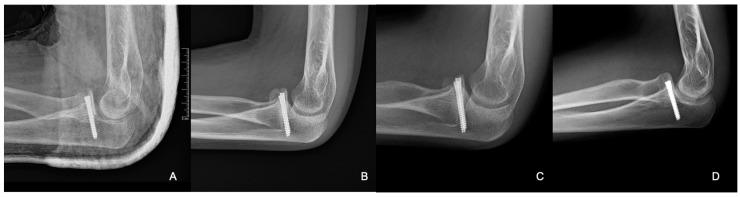

小儿冠状突骨折的手术治疗:两例报告

Surgical Management of Pediatric Coronoid Process Fractures: A Report of Two Cases.

Coronoid process fractures in the pediatric population are rare and often misdiagnosed, leading to chronic elbow instability. We aim to evaluate the surgical management of two adolescent cases of inveterate coronoid fractures using autologous bone grafting. Both patients, with a history of recurrent elbow dislocations, presented with pseudoarthrosis and were initially misdiagnosed due to minor or subtle fractures. Comprehensive imaging, including computed tomography (CT) and magnetic resonance imaging (MRI), confirmed the presence of significant coronoid defects. The surgical intervention involved employing autografts from the iliac wing to reconstruct the coronoid process, followed by fixation with screws. Both patients underwent postoperative rehabilitation via physiotherapy, resulting in full functional recovery. At their one-year follow-ups, both patients regained full elbow function, achieving range-of-motion measurements of 0-0-130° flexion-extension and 90-0-90° pronation-supination; no recurrence of instability was reported, with no complications at the yearly follow-ups. This approach demonstrates the efficacy of autograft reconstruction in restoring elbow stability, particularly in cases with substantial bone loss or pseudoarthrosis. Our study highlights the importance of advanced imaging and individualized treatment strategies, emphasizing that early surgical intervention can prevent long-term disability in pediatric patients with chronic coronoid fractures.

摘要

小儿冠状突骨折较为罕见,且常被误诊,从而导致慢性肘关节不稳定。我们旨在评估两例青少年陈旧性冠状突骨折采用自体骨移植的手术治疗方法。两名患者均有复发性肘关节脱位病史,表现为假关节形成,最初因骨折轻微或不明显而被误诊。包括计算机断层扫描(CT)和磁共振成像(MRI)在内的综合影像学检查证实存在明显的冠状突缺损。手术干预包括采用来自髂骨翼的自体骨移植来重建冠状突,随后用螺钉固定。两名患者术后均通过物理治疗进行康复,最终实现了功能完全恢复。在一年的随访中,两名患者均恢复了完全的肘关节功能,屈伸活动度达到0-0-130°,旋前旋后活动度达到90-0-90°;未报告不稳定复发情况,年度随访也未出现并发症。这种方法证明了自体骨移植重建在恢复肘关节稳定性方面的有效性,特别是在存在大量骨质流失或假关节形成的病例中。我们的研究强调了先进影像学检查和个体化治疗策略的重要性,强调早期手术干预可以预防慢性冠状突骨折小儿患者的长期残疾。